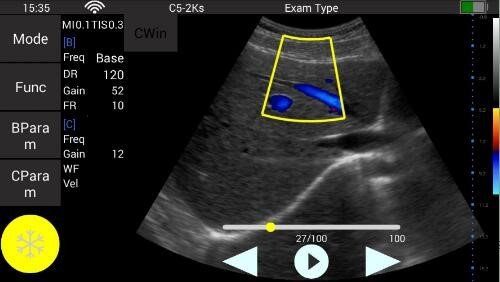

Konvexsonde (C5-2Ks) 3,3 MHz 2 - 5 MHz R50 Abdomen, Gynäkologie, Geburtshilfe, Urologie

• Color: B, M, 2B, 4B, THI, Color, Power, PW